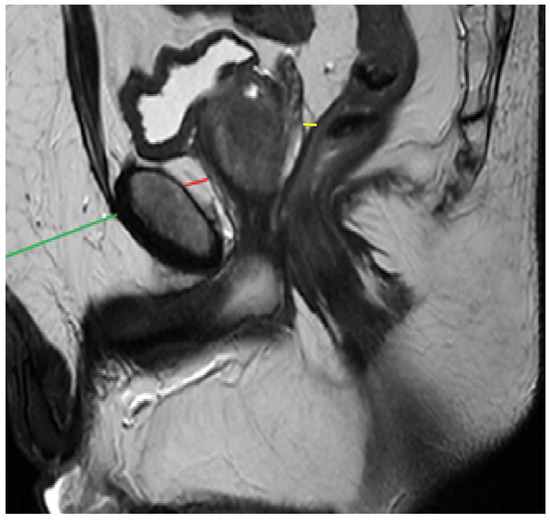

For all patients, PPAT thickness (PPATT), posterior periprostatic adipose tissue thickness (PPPATT), and subcutaneous adipose tissue thickness (SATT) were measured on T2-weighted MRI images by a radiologist with experience in prostate MRI using RadiAnt DICOM Viewer 2025.2 (Medixant: Poznań, Poland, https://www.radiantviewer.com/). T2W images not only provide clear visualization of fat distribution, but also represent the most appropriate sequence for such measurements and are one of the core components of biparametric MRI protocols. In addition to these linear measurements, volumetric analysis of periprostatic adipose tissue was also performed, providing a more comprehensive evaluation of fat distribution. This dual approach allowed for both simplified morphometric assessment and a more nuanced spatial quantification of adiposity. The image below represents a schematic sagittal MRI view of the male pelvic region (Figure 1).

Figure 1. Schematic sagittal section of the male pelvis on MRI.